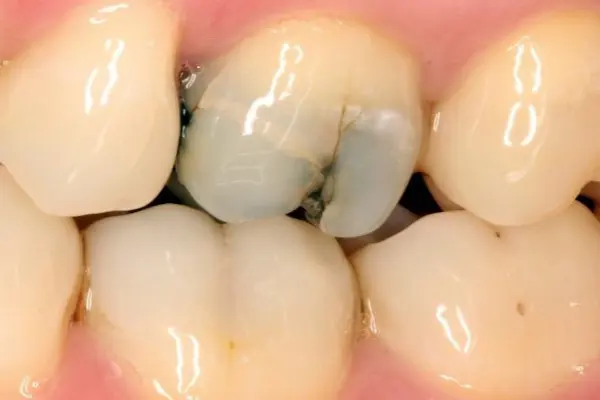

Cracks under fillings

Your dentist may find cracks under your old fillings. After the filling is removed from the tooth, they can see the cracks located under the filling and inside the tooth. Sometimes, cracks can cause other parts of the tooth to fall off when the filling is removed. This is more common with amalgam fillings. There are a few reasons that cracks develop under amalgam fillings.

- Amalgam fillings are made of metal. The metal expands and shrinks a little bit every time it is contacted by hot and cold temperatures. These changes put pressure on the tooth and may lead to cracks.

- Amalgam fillings do not stick to teeth like tooth-coloured fillings. The dentist cuts a cavity in the tooth that will hold the filling in place. More tooth needs to be removed for amalgam fillings. This may lead to some tooth structure around the filling getting weak over time.